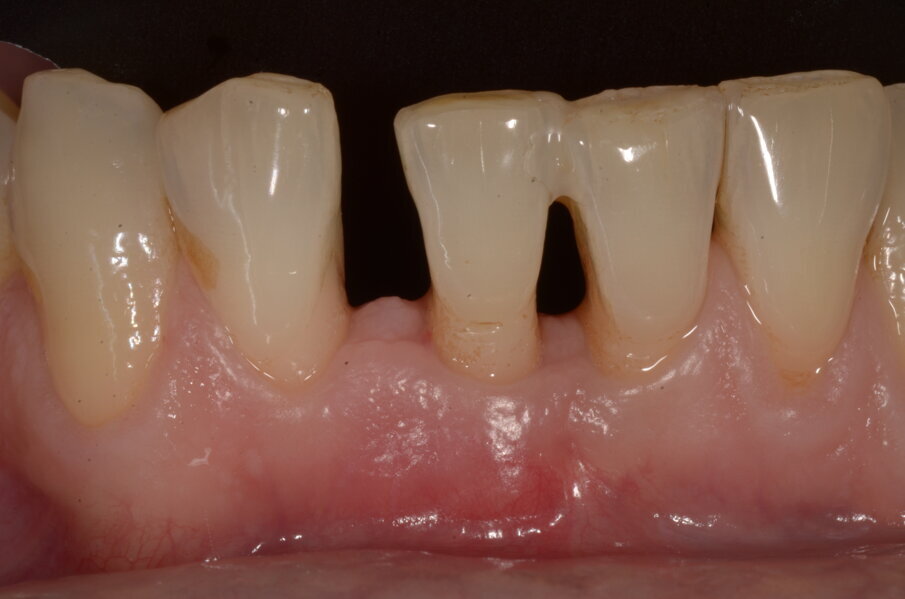

Figg. 6a, 6b - Sondaggio iniziale del difetto.

Il Paziente è stato intercettato in visita con diagnosi di parodontite cronica generalizzata da moderata a severa a seconda dei siti. È stata eseguita la terapia non chirurgica in regime di Full mouth disinfection in unica seduta seguita da controlli settimanali fino al raggiungimento della guarigione a 2 mesi dalla strumentazione. In tale fase sulla base della valutazione dei siti con PD>5 mm e dell’anatomia dei difetti infra-ossei o sovra ossei presenti viene normalmente discussa con il paziente la fase di chirurgia correttiva, se necessaria. Nel Paziente in questo caso residuava a livello di 41 un difetto infra-osseo (Figg. 6a-6c).